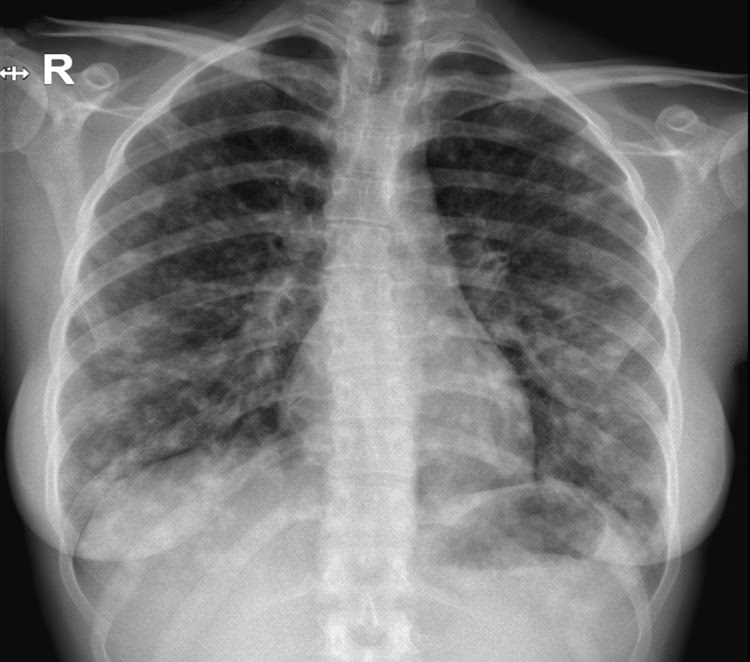

- Røntgenbillede af brystkassen: Dette er en afgørende undersøgelse, der kan visualisere infektionen. Lægen vil kigge efter hvide pletter (infiltrater) på billederne, og deres tilstedeværelse i begge lunger bekræfter diagnosen bilateral lungebetændelse.